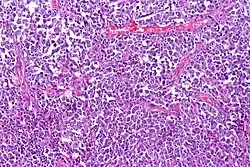

Histological sample of diffuse large B-cell lymphoma (DLBCL)

Lymphoma cancer types have varying probabilities of metastasizing to the CNS, resulting in secondary CNS lymphoma (SCNSL), which may appear simultaneously as systemic lymphoma, or as remission after systemic lymphoma is treated. Synchronous, or de novo disease is diagnosed in approximately 40% of patients and relapse in 60%.[8] Overall, CNS involvement is observed in 2 to 27% of patients with aggressive systemic non-Hodgkin's lymphoma.[5] 5% of patients with diffuse large B cell lymphoma, the most common type of non-Hodgkin lymphoma, result in SCNSL but account for most SCNSL cases.[3]